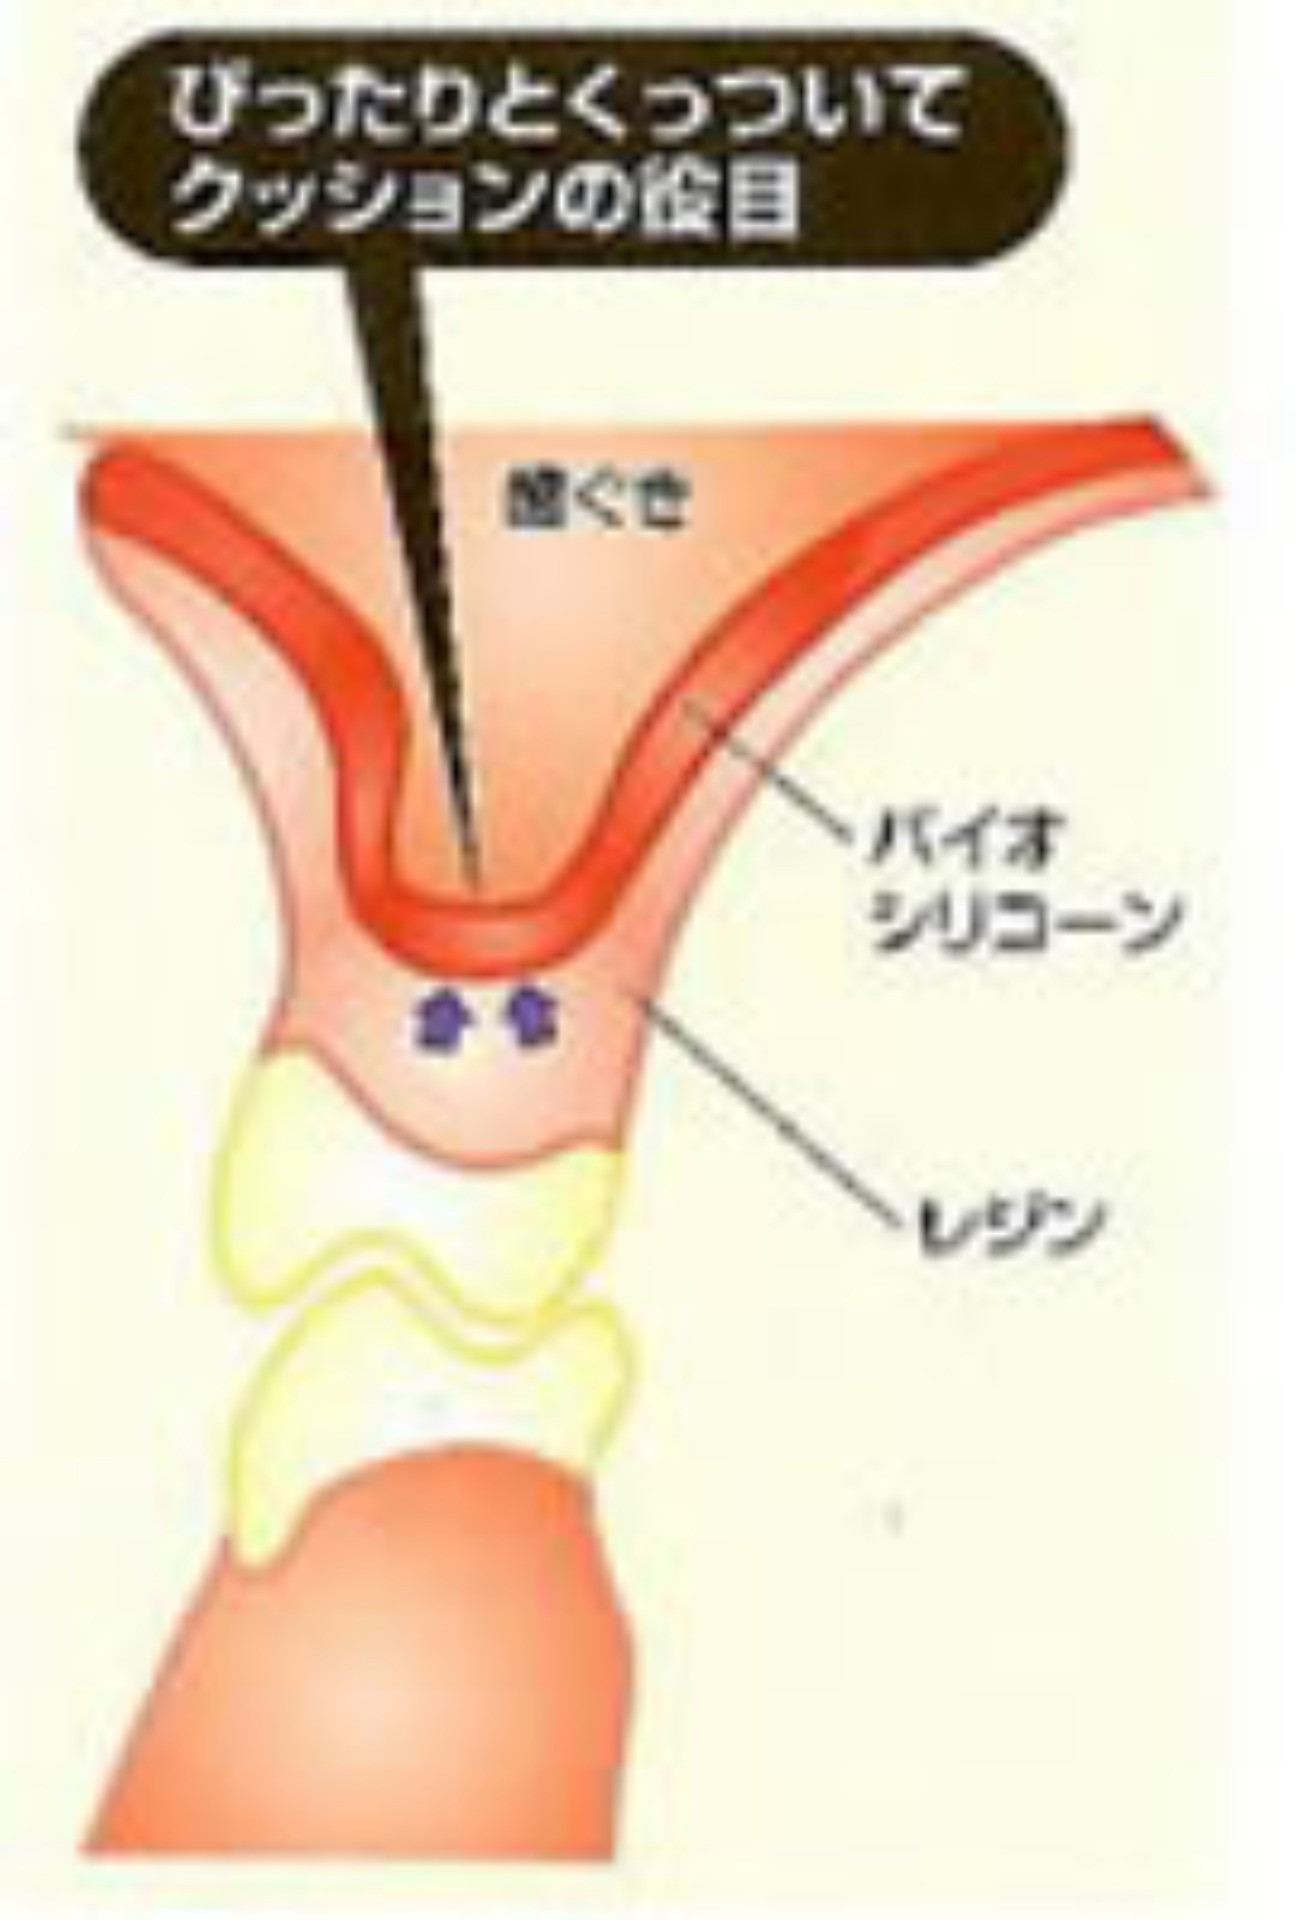

ソフトデンチャーとは、義歯の内面に、やわらかい生体用バイオシリコンを使用しており、歯茎や歯にぴったりと合い、隙間が少ない為、食べかすがはさまりにくく、バイオシリコンで安定させるため、金具の見えないタイプの義歯も可能です。

ソフトデンチャーは歯ぐきに接触する面に特殊加工を施した入れ歯です。弾力性のある軟性樹脂(シリコン状の素材)を使用しているため歯ぐきに加わる負担を軽減させ痛みを感じません。 |

体温により軟化し歯ぐきに吸い付きます。顎の骨が薄くなった方や入れ歯が合わない方にお勧めいたします。 |